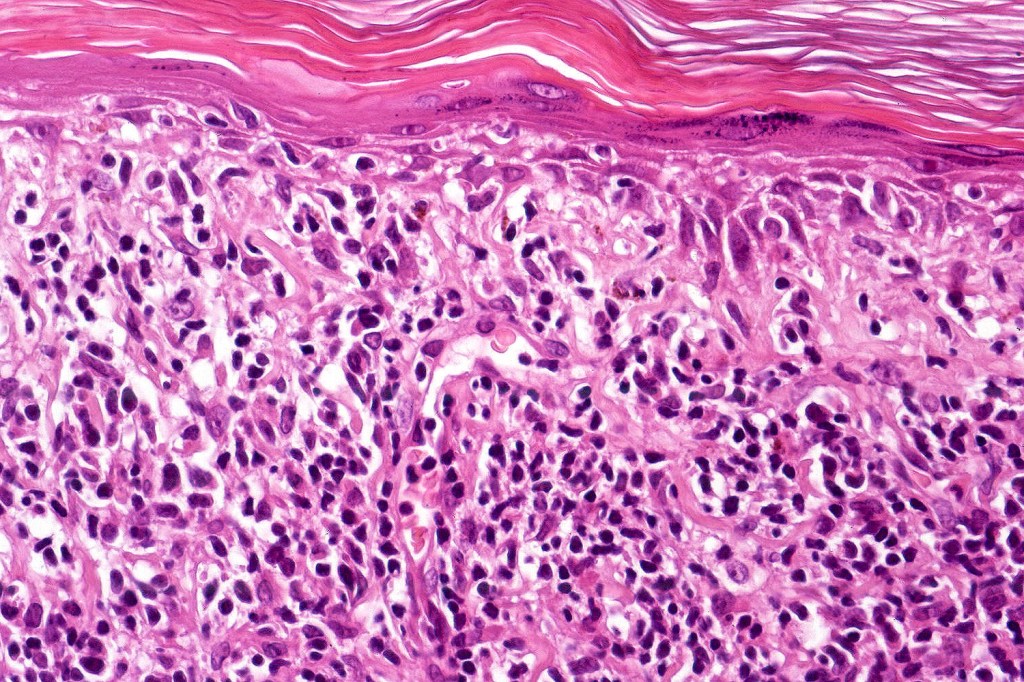

Histological features

The histological hallmark of mycosis fungoides is the presence of large atypical lymphocytes with a convoluted/cerebriform nuclear border (Sézary cells). These may be found at the epidermal-dermal jnuction and as collections within the epidermis (Pautrier microabscess). These are most easily found in plaque stage disease. The epidermal component can be subtle in patch stage disease and is often lost in tumor stage dsease. The classification into patch, plaque & tumor stage disease is less helpful histologically as the features merge from one to the other. It is all a matter of degree.

Plaque Stage Disease

•Compact hyperkeratosis & patchy parakeratosis

•Acanthosis

•Psoriasiform hyperplasia common

•Epidermotropism is often marked with conspicuous Pautrier microabscesses

•Lichenoid variant & poikiloderma atrophicans vasculare

•Variable folliculotropism (+/- mucinosis) & syringotropism

•Coarse collagen bundles in papillary dermis

•Superficial band-like dermal infiltrate of atypical lymphocytes, eosinophils, plasma cells & histiocytes